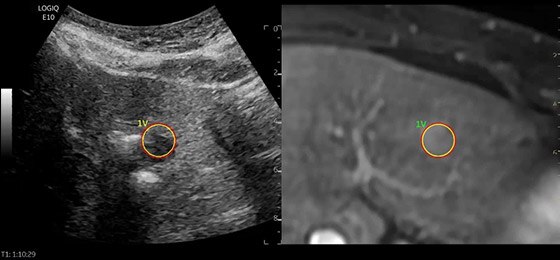

Liver Biopsy with five-angle Verza** needle guide

Clinicians need an ultrasound system that will help them identify high-risk liver cancer patients, track disease progression, and make informed decisions to optimize treatment efficacy.